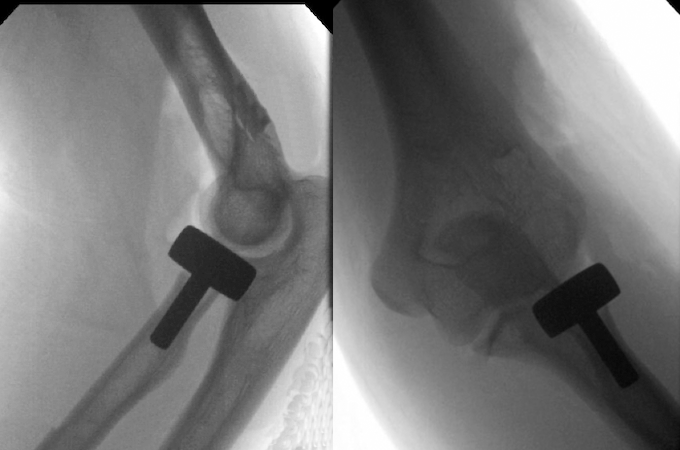

Treatment

- TTIs nearly always require surgery, and most experts recommend early surgical intervention to improve the odds of a successful outcome.4,15

- Surgery typically includes radiocapitellar joint restoration and reattachment of the lateral collateral ligament (LCL), while coronoid fracture fixation and MCL repair may also be performed in some cases.13

- Several approaches can be used to address coronoid fractures in TTIs, and since there is no consensus on which approach is best, decisions should be made based on fragment size and fracture location.

- For comminuted radial head fractures, either fixation or artificial replacement can be performed.